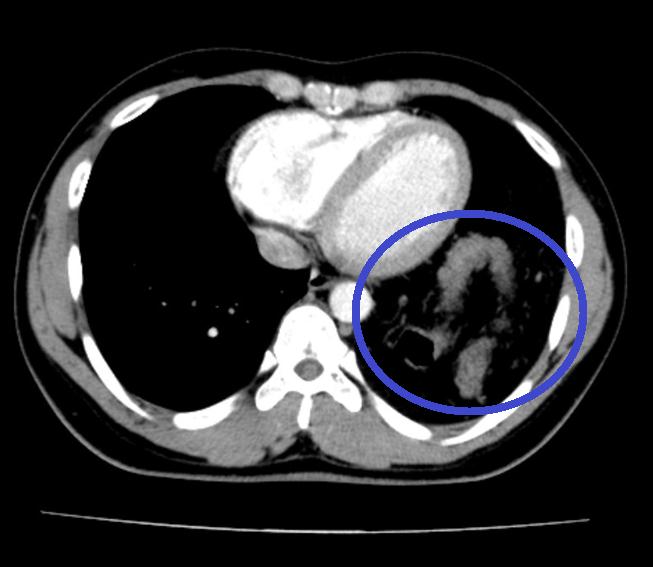

Các bác sĩ tiến hành nội soi ổ bụng cho bệnh nhân và phát hiện toàn bộ đại tràng ngang, lách, dạ dày và mạc nối lớn của bệnh nhân đã chui qua cơ hoành lên khoang màng phổi bên trái. Bệnh nhân được chẩn đoán thoát vị hoành trái do vỡ cơ hoành và có chỉ định phẫu thuật.

BS Nguyễn Huy Du - Khoa Phẫu thuật Tiêu hóa - Gan Mật Tụy, Bệnh viện Bạch Mai cho biết: Thoát vị hoành do chấn thương là tình trạng một hoặc nhiều tạng nằm trong ổ bụng bị kéo lên ngực thông qua vết rách cơ hoành. Cơ hoành bình thường là vách ngăn kín giữa lồng ngực và ổ bụng, có thể bị rách vỡ khi bị những chấn thương làm tăng áp lực đột ngột trong ổ bụng. Những trường hợp này chiếm khoảng 8% các trường hợp chấn thương nặng và phổ biến nhất ở nam thanh niên trong các vụ TNGT.

Có khoảng 15% trường hợp bị vỡ cơ hoành chẩn đoán muộn do tổn thương không dẫn đến thoát vị ngay lập tức. Có thể tìm thấy dạ dày, mạc nối, ruột non, đại tràng, lách và thậm chí cả thận trong thoát vị hoành do chấn thương.